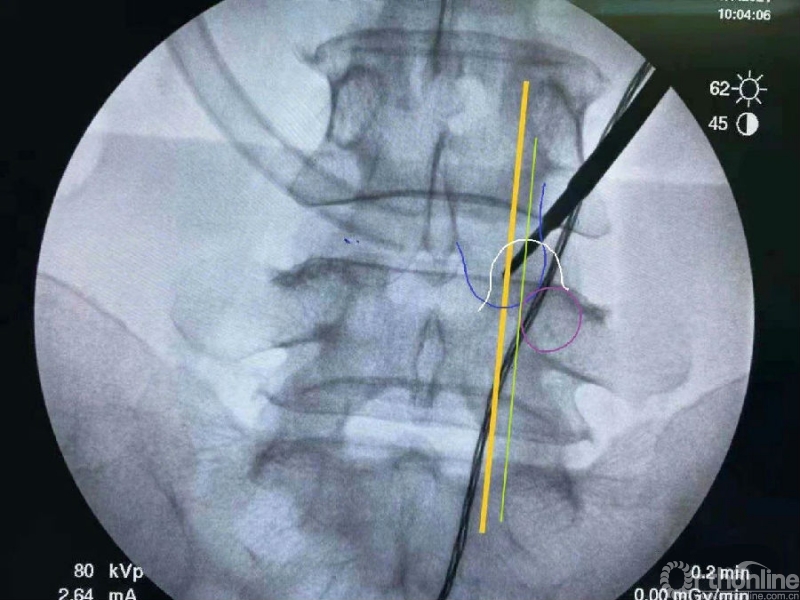

内镜监视下使用mark小磨钻进行第一定位,发现定位线过于偏内。

然后在内镜监视下于第一个孔的外侧进行第二次定位。

第二次定位虽然并位于椎弓根内缘线上,但是我们觉得本病历参考内缘线的话可能会把下关节突的2/3磨掉,所以我们选择第二个接近椎弓根内缘线的定位孔作为镜下下关节突内缘切除的外界。